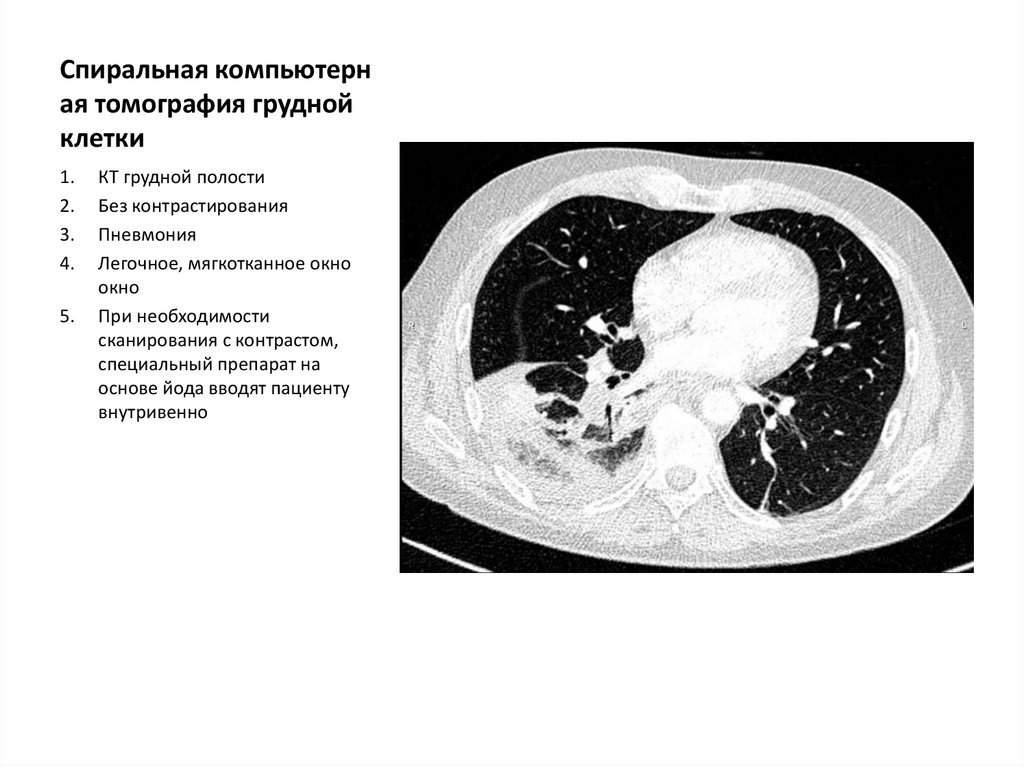

Спиральная компьютерн

ая томография грудной

клетки

КТ грудной полости

Без контрастирования

Пневмония

Легочное, мягкотканное окно

окно

При необходимости

сканирования с контрастом,

специальный препарат на

основе йода вводят пациенту

внутривенно